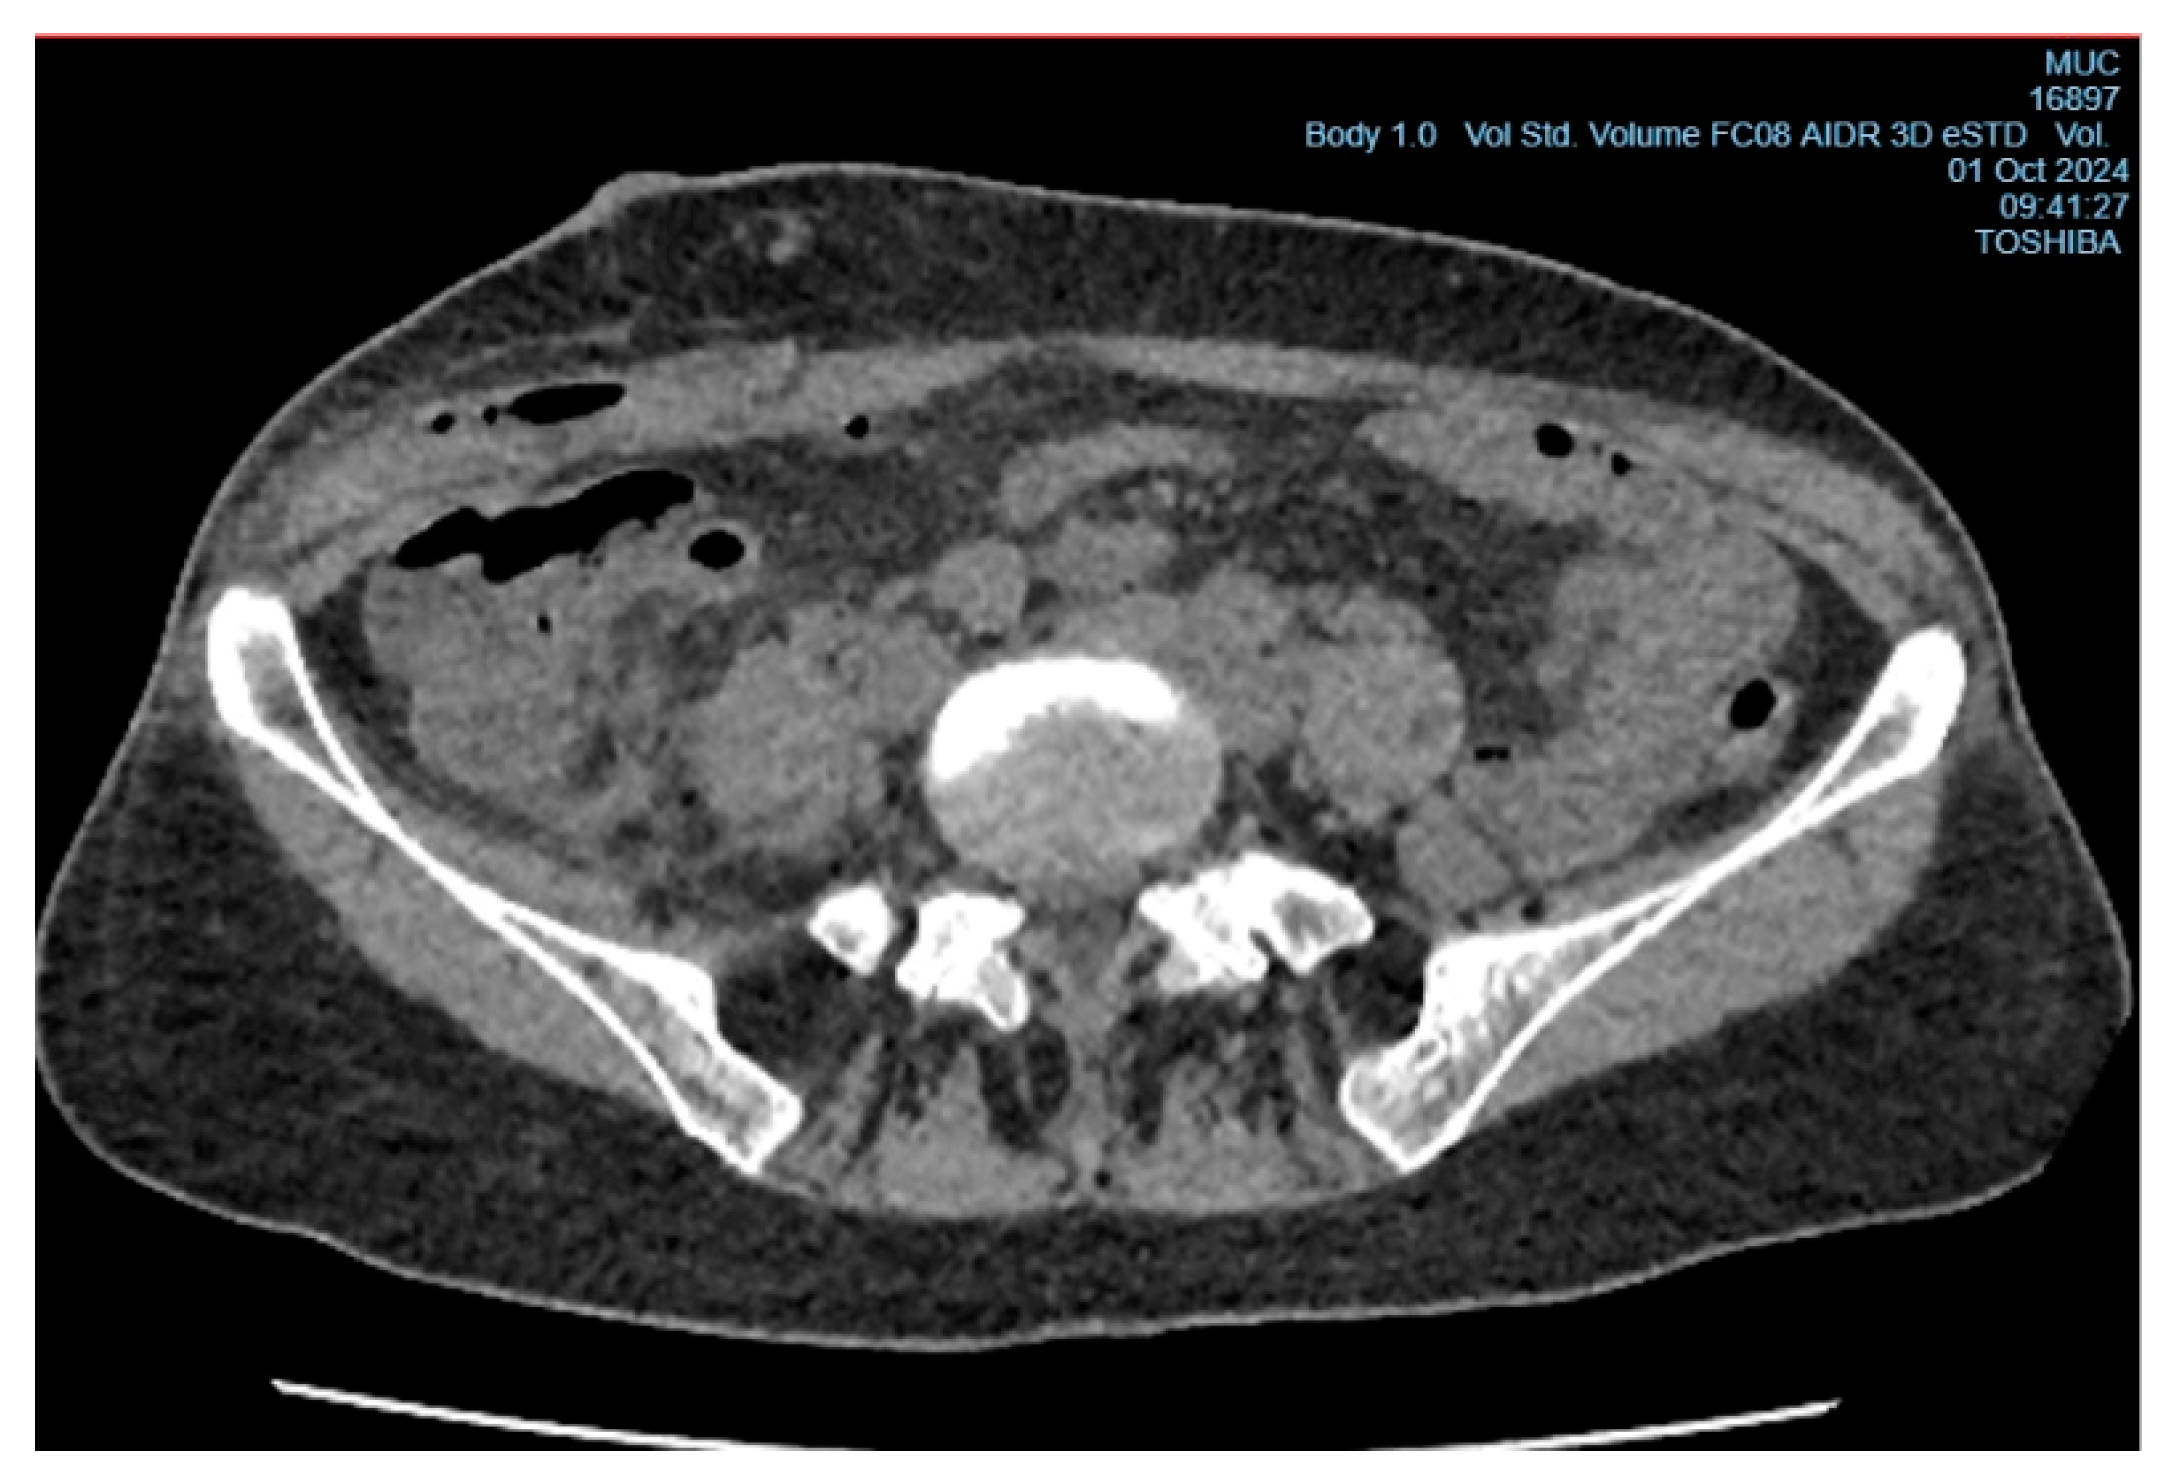

In the early postoperative period, the patient had a persistent elevated body temperature of 37.5°C–38.0°C, localized tenderness at the site of the surgical wound, but no local hyperemia. Leukocytosis was observed (11.2×10⁹/L, reference range from 4 to 9×10⁹/L) with an increase in neutrophils (neutrophils - 78%, reference range from 35% to 70%, band neutrophils - 4%, reference range from 1% to 5%). Despite antibacterial therapy (Cef III, 1.0 gram intramuscularly twice daily), no clinical improvement was observed, raising suspicion of a subgaleal abscess of the postoperative wound (Figure 3). On the 6th day after surgery, the patient underwent wound revision under local anesthesia with 0.5% Novocain solution (30 ml). During the procedure, a collection of pus under the aponeurosis of the external oblique abdominal muscle was diagnosed, and the abscess cavity was drained (Figure 4). A sample for microbiological analysis was collected and sent to the research laboratory of the Karaganda Medical University.

In accordance with the results of sensitivity testing to antibacterial drugs, the patient was prescribed ceftriaxone in a dose of 1.0 g intramuscularly 2 times a day, daily dressings with antiseptic solutions. On the background of the treatment positive dynamics was noted: the main complaints regressed, body temperature normalized. In the control analyses the level of leukocytes was 7×109/l. The postoperative wound was cleared of purulent discharge, edema and hyperemia regressed, the postoperative wound was tightened by secondary tension, with active growth of granulation tissue. The patient was discharged in satisfactory condition. Bacteriologic culture was repeatedly taken from the area of the postoperative wound, as a result of which A. odontolyticus was not identified, indicating a positive effect of treatment and complete elimination of this pathogen.

Figure 4. CT image after the drainage of the subgaleal abscess.